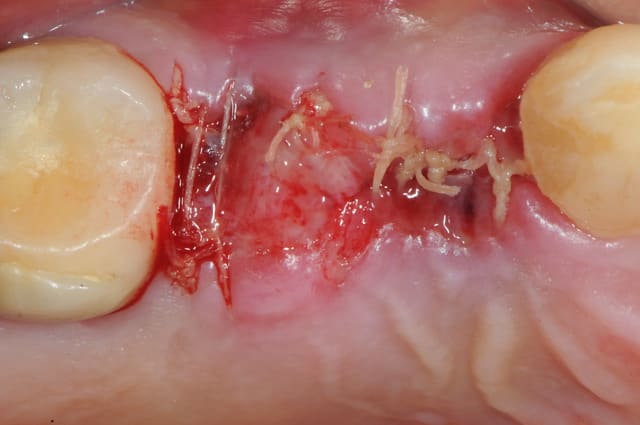

résultat à j+5

c'est pas si mal, le "greffon" est rose et ne semble pas s'être nécrosé.

attendons encore 3 mois..